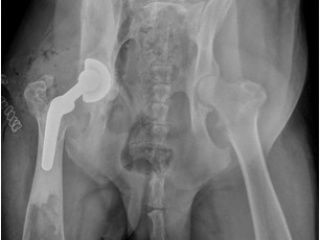

Prise en charge des dysplasies (hanche, coude), des boiteries et traumatismes : TPLO, prothèse totale de hanche, arthroscopie mini-invasive pour les lésions du coude (FCPM) et autres articulations.

Le Centre Hospitalier VetOccitanie est spécialisé dans le traitement des maladies et traumatismes orthopédiques et articulaires.

Traitement des dysplasies ou anomalies articulaires

- Dysplasie de la hanche: Symphysiodèse pubienne, Triple ostéotomie du bassin, Prothèse totale de hanche